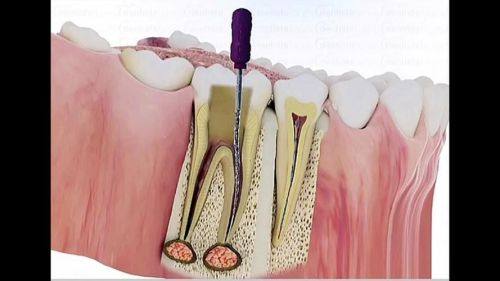

前牙根管治疗:580元起

后牙根管治疗:980元起